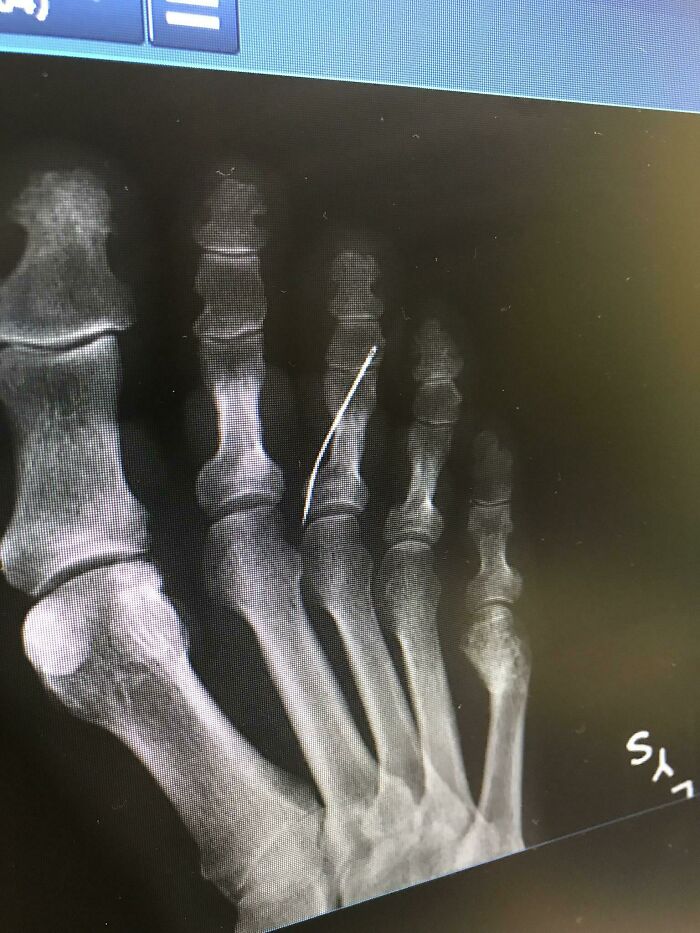

#70 My Grandma Had No Idea She Had A Sewing Needle In Her Foot. No Telling How Long It’s Been In There. Skin Was Healed. It Finally Started Rejecting Yesterday And She Had Emergency Surgery

Image credits: kaylalorene